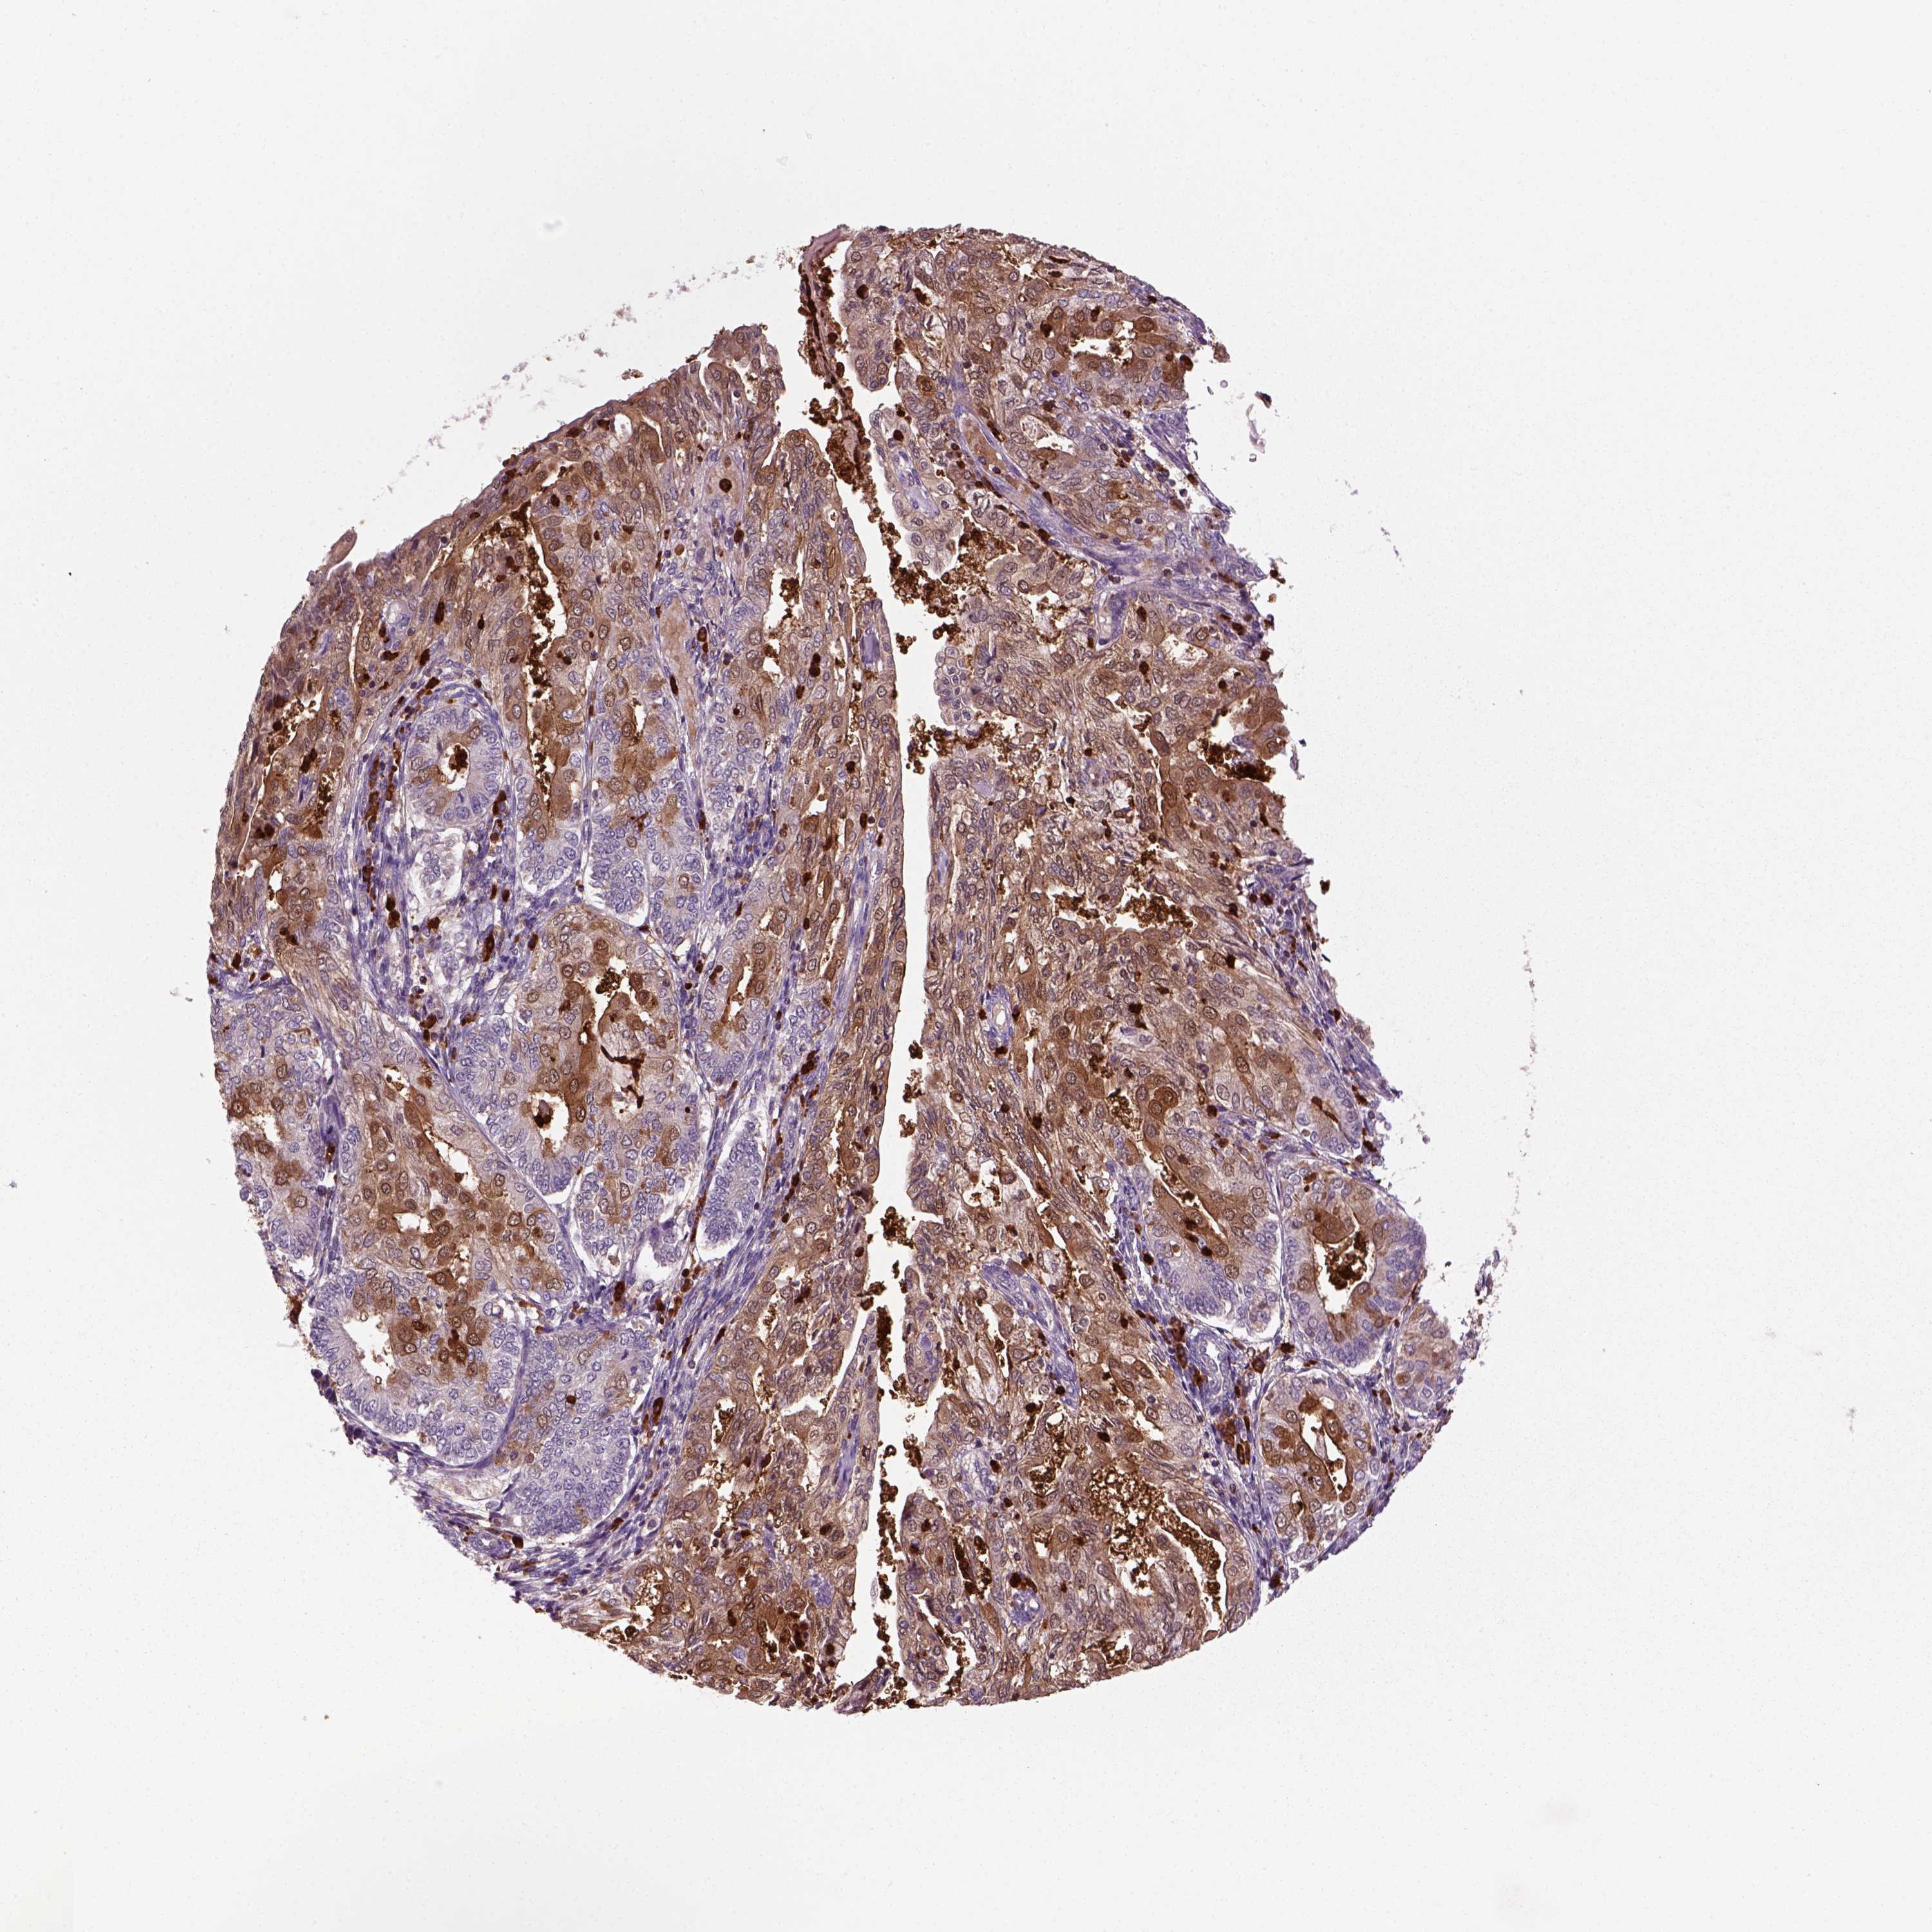

ENDOMETRIAL CANCER - Protein expressioni

A mouse-over function shows sample information and annotation data. Click on an image to view it in a full screen mode. Samples can be filtered based on level of antibody staining by selecting one or several of the following categories: high, medium, low and not detected. The assay and annotation is described here.

Note that samples used for immunohistochemistry by the Human Protein Atlas do not correspond to samples in the TCGA dataset.

Antibody stainingi

Antibody staining in the annotated cell types in the current human tissue is reported as not detected, low, medium, or high, based on conventional immunohistochemistry profiling in selected tissues. This score is based on the combination of the staining intensity and fraction of stained cells.

Each image is clickable and will lead to virtual microscopy that enables deeper exploration of all samples and also displays staining intensity scores, fraction scores and subcellular localization as well as patient and tissue information for each sample.

Antibody HPA044186

Antibody HPA063605

Staining

High

Medium

Low

Not detected

Intensity

Strong

Moderate

Weak

Negative

Quantity

>75%

75%-25%

<25%

None

Location

Nuclear

Cytoplasmic/membranous

Cytoplasmic/membranous,nuclear

Adenocarcinoma, NOS